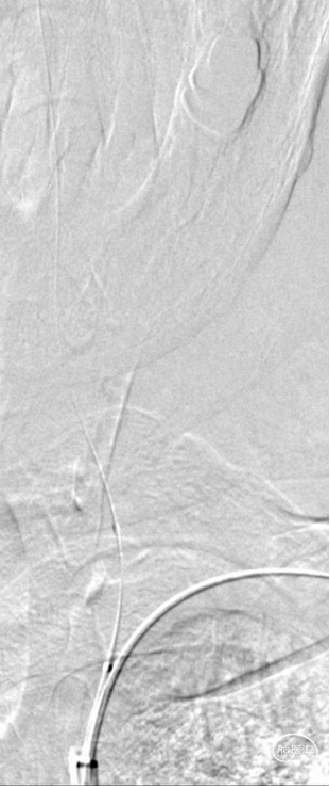

造影结果:

患者左侧锁骨下动脉重度狭窄伴斑块形成,左侧椎动脉开口处次全闭塞,右侧椎动脉开口处中重度狭窄,右侧后交通动脉发达。

微导丝、球囊到位:

置入0.018inch*300cm微导丝至锁骨下远端,以0.014inch*200cm微导丝携带0.017inch微导管通过狭窄段,置入V2段,微量造影确认位于血管真腔,以0.014inch*300cm微导丝行长导丝交换技术将2.0mm×20mm球囊扩张导管部分送至左侧椎动脉狭窄段。